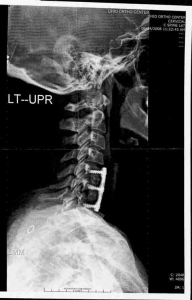

7. In 2008, after suffering pain, burning and numbness in my face, neck, shoulder, arms and hands, with loss of fine motor skills in my hands/fingers, I was diagnosed with a completely dessicated C-6/7 and a nerve-compressing herniation at 5/6. Orthopod performed dual discectomy and fusion with plate and screws. He informed me my pain tolerance was very high and I should be cautious of anything ‘uncomfortable’ vs. letting things become painful before seeking medical care. He tried Flexeril (and then Amrix), Mobic, and Vicodin as needed for 3 months before surgery. I asked if I would participate in physical therapy after surgery, but he said no the surgery should fix everything. There was no trauma, no accident, no specific injury that lead to this situation. Doc even diagnosed ‘undetermined’ for the cause. Seems a bit unusual to do that much damage and not want to find or diagnose a cause?!?

Last week my primary sent me for X-ray (TMJ specific) and a new C-spine MRI. She also ordered a TMJ specific MRI but that has not yet been scheduled. Waiting for the doc to call for my follow up post radiologist report. A good friend of mine is a radiologist in CA, so I sent him a copy of my films, and anecdotally (as a friend and I realize it’s not considered the best practice) he noted what appears to be a significant herniation at C-3/4 on the MRI. The x-rays were not of very good quality and he suggested I may need new films, but he said it was clear that my disc is no longer recognizable in the TMJ joints, there is significant condyle (sp) degredation and evidence of adhesions.

Attached the x-ray taken a few weeks after the fusion 09 June 2008. What lordosis, ha!?! Sorry that IS humor albeit sarcasm…if we can’t laugh at ourselves…… ;0)

I agree with you 100% that your X-Ray tech just radiated you for nothing. Spine is a weight bearing structure and responds to weight bearing stresses. You could see better what is going with the spine when you shoot X-Rays in a standing position. Full spine X-Ray is an optimal if possible. Lower back problems are related to your neck problems. Every single subluxation and curve in a cervical, thoracic and lumbar spine must be taken into consideration in order to achieve the best results possible. I would not expose myself a second time to an additional dose of radiation at this point and time. The is still a small presence of cervical lordosis which is a positive sign. There is nothing that can be done at this point and time with your lower cervical spine. Sorry to say, but too much damage has been done by your orthopedic surgeon. The goal at this point is to keep the vertebraes and IVD (Intervertebral discs) from degenerating farther. If I would be you I would get these two products: #1. Bodyline BDL127 The Neck Decompressor and #2 Posture Pro Corp. POS107 Deluxe Full Spine Posture Pump Model 4100